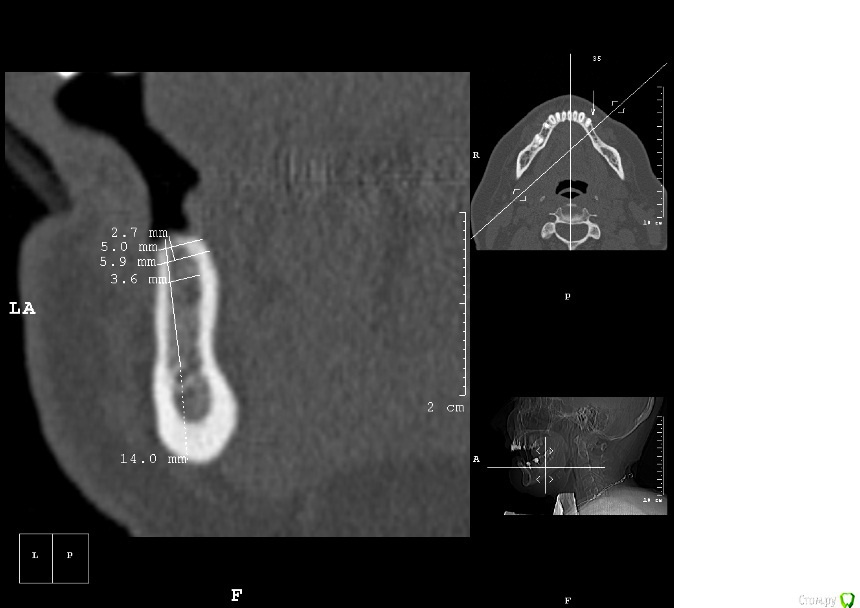

kamranchick Опубликовано 2 мая, 2016 Автор Поделиться Опубликовано 2 мая, 2016 ну я указал 3 сегмент, 3 винта, следовательно удаление 5 го зуба, установка имплантатов в область 35 36 и 37 Ссылка на комментарий

dantist_movani Опубликовано 2 мая, 2016 Поделиться Опубликовано 2 мая, 2016 Ось имплантата в проекции 3.7 слишком язычная, так же имплантат устанавливали? Ссылка на комментарий

dantist_movani Опубликовано 2 мая, 2016 Поделиться Опубликовано 2 мая, 2016 Спасибо, ответы давно уже получил, и дело не в срезах вовсе, чем вам срезы не угодили?на срезах указаны позиции 3.5,3.6,3.7,3.8? В какие позиции "3 винта" и что удалить, я просто может не понял? Ссылка на комментарий